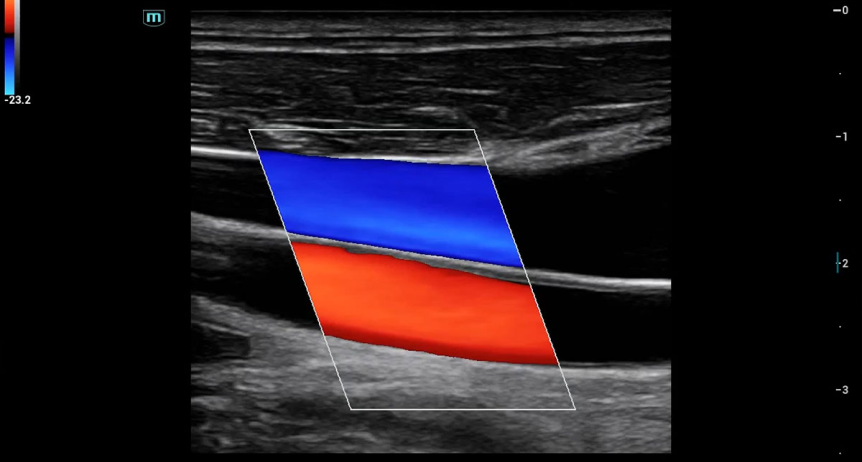

CAROTIDA Y VENA JUGULAR